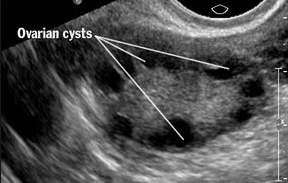

What is PCOS

First line treatment = WEIGHT LOSS then metformin (insulin sensitiser), CC, FSHn or IVF